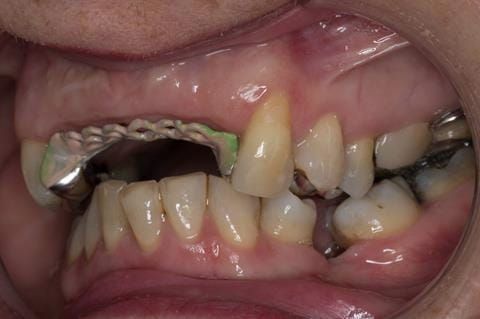

Provision of a maxillary cobalt chromium based partial denture/protective occlusal splint in a heavily restored dentition

- UR2 peri-radicular periodontitis with a peri-radicular area on the root apex. Retrograde amalgam filling from a previous apicectomy. No visible root canal or root canal filling. Large circumferential marginal gap between the crown and tooth. Large post and core present. Very little tooth structure remaining resulting in a fragile tooth with increased potential for fracture.

- UR1 peri-radicular periodontitis with a small peri-radicular area on the root apex with wide blunderbuss apex. Radio-opaque root canal filling present approximately 3 mm short of the radiographic apex. Large circumferential marginal gap between the crown and tooth. Large post and core present. Very little tooth structure remaining resulting in a fragile tooth with increased potential for fracture.

- UL1 peri-radicular periodontitis with a peri-radicular area on the root apex. Retrograde amalgam filling from a previous apicectomy. Visible root canal space with no sign of root canal filling. Large circumferential marginal gap between the crown and tooth. Large post and core present. Very little tooth structure remaining resulting in a fragile tooth with increased potential for fracture.

- UL2 peri-radicular periodontitis with a peri-radicular area on the root apex. No visible root canal or root canal filling. Large circumferential marginal gap between the crown and tooth. Large post and core present. Very little tooth structure remaining resulting in a fragile tooth with increased potential for fracture.

- High smile line showing gum above gingival zeniths of upper front teeth when smiling. Aesthetic failure of the upper four incisors with inflammation of the gingivae and mis-match of the gingival zenith levels.

- Other than the maxillary incisors the remaining dentition was in marginally better condition being moderately to heavily restored. Many will probably require replacement and restoration from time to time mainly from wear and tear owing to occlusal forces.

Following consultation and second discussion appointment the patient chose to have option 3 namely, a maxillary cobalt chromium based partial denture/protective occlusal splint. The clinical situation and treatment process is shown in detail below with photographs. The patient was successfully rehabilitated with this and her quality of life considerably improved. The clinical work was provided by Finlay and the technical work by Rowan.